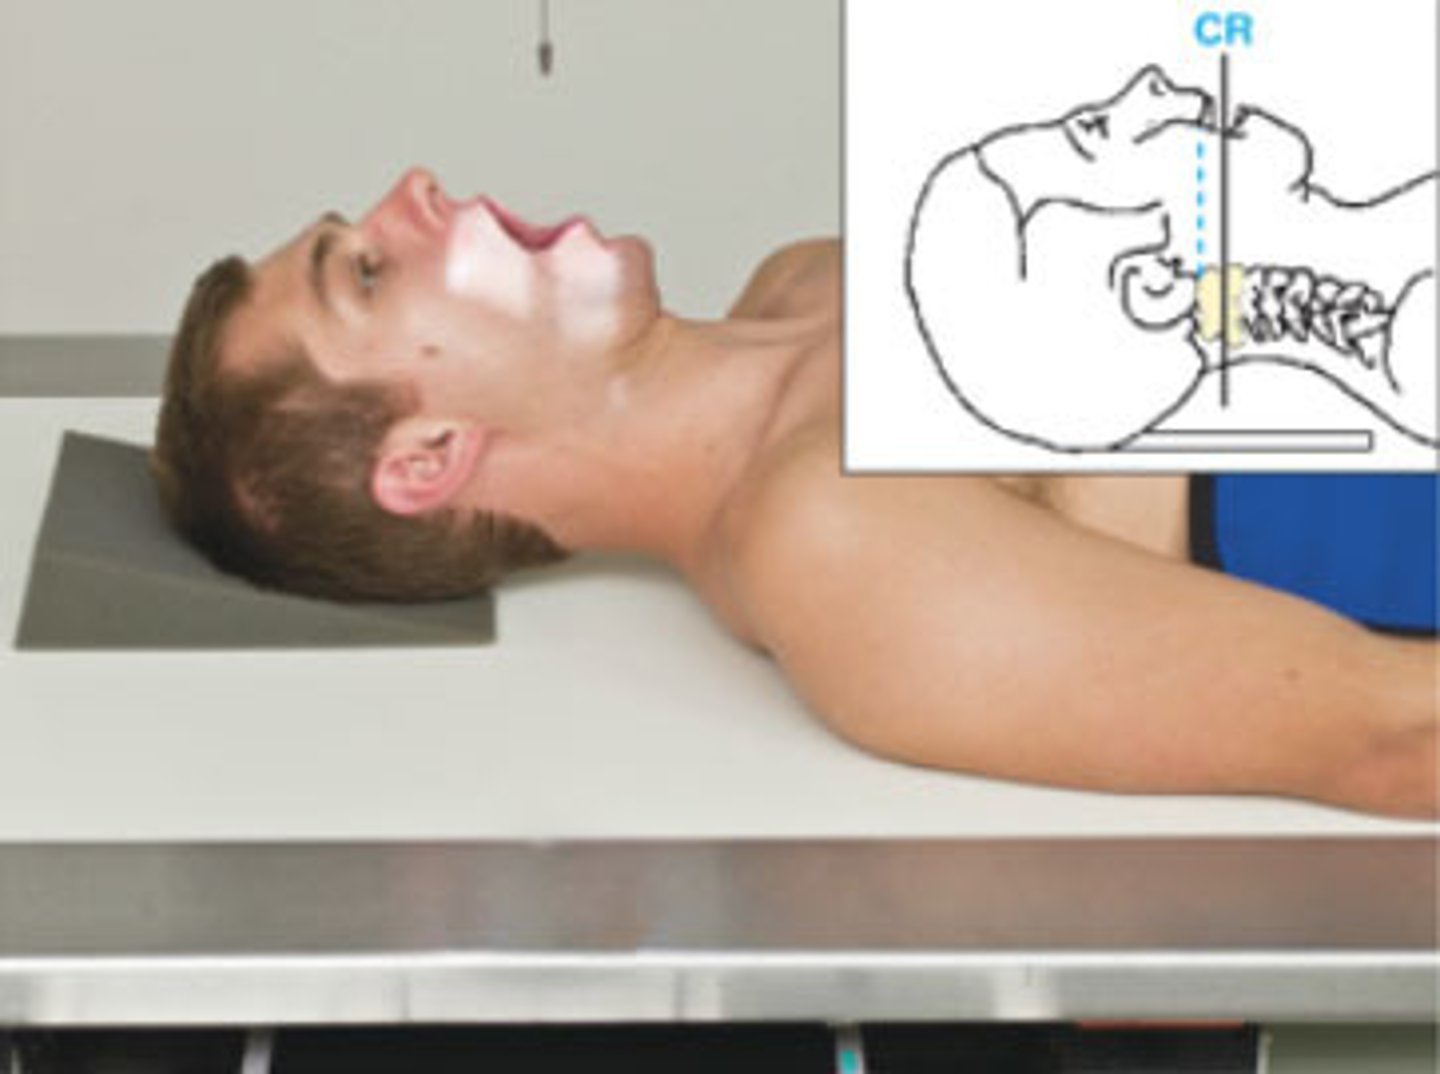

Go through the STAMPSBC list for the AP Open Mouth C-spine

S - shielding around waist

T - 40 mAs @ 75 kVp

A - no angle

M - marker along skin line of neck

P - back against board, bottom of front teeth line up w/ base of skull

S - 40

B - suspended breathing

C - 10 x 12 lengthwise, can collimate to 7 x 7

Where do you center for the AP Open Mouth C-spine?

center of mouth

What does the AP Open Mouth C-spine demonstrate?

C1 - C2 articulation